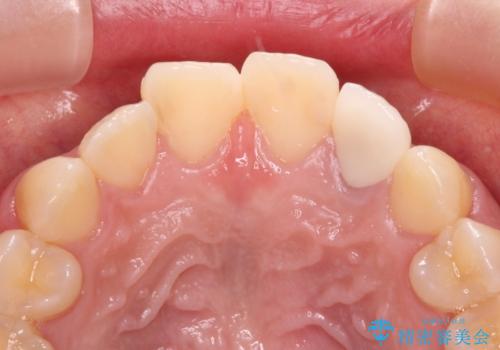

- 根管治療後に10年以上経過し、変色した前歯を気にして来院された患者様です。

根管治療はやり直さずに、ファイバーポストを使用した土台を植立してオールセラミッククラウンにて補綴することとしました。